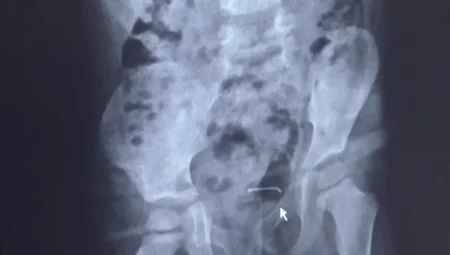

Bitlis’te 5 Yaşındaki Çocuğun Mesanesinden Çıkan Cisim Şaşkına Çevirdi

Bitlis’in Güroymak ilçesinde karın ağrısı şikayetiyle hastaneye götürülen 5 yaşındaki çocuğun mesane duvarında metal bir…